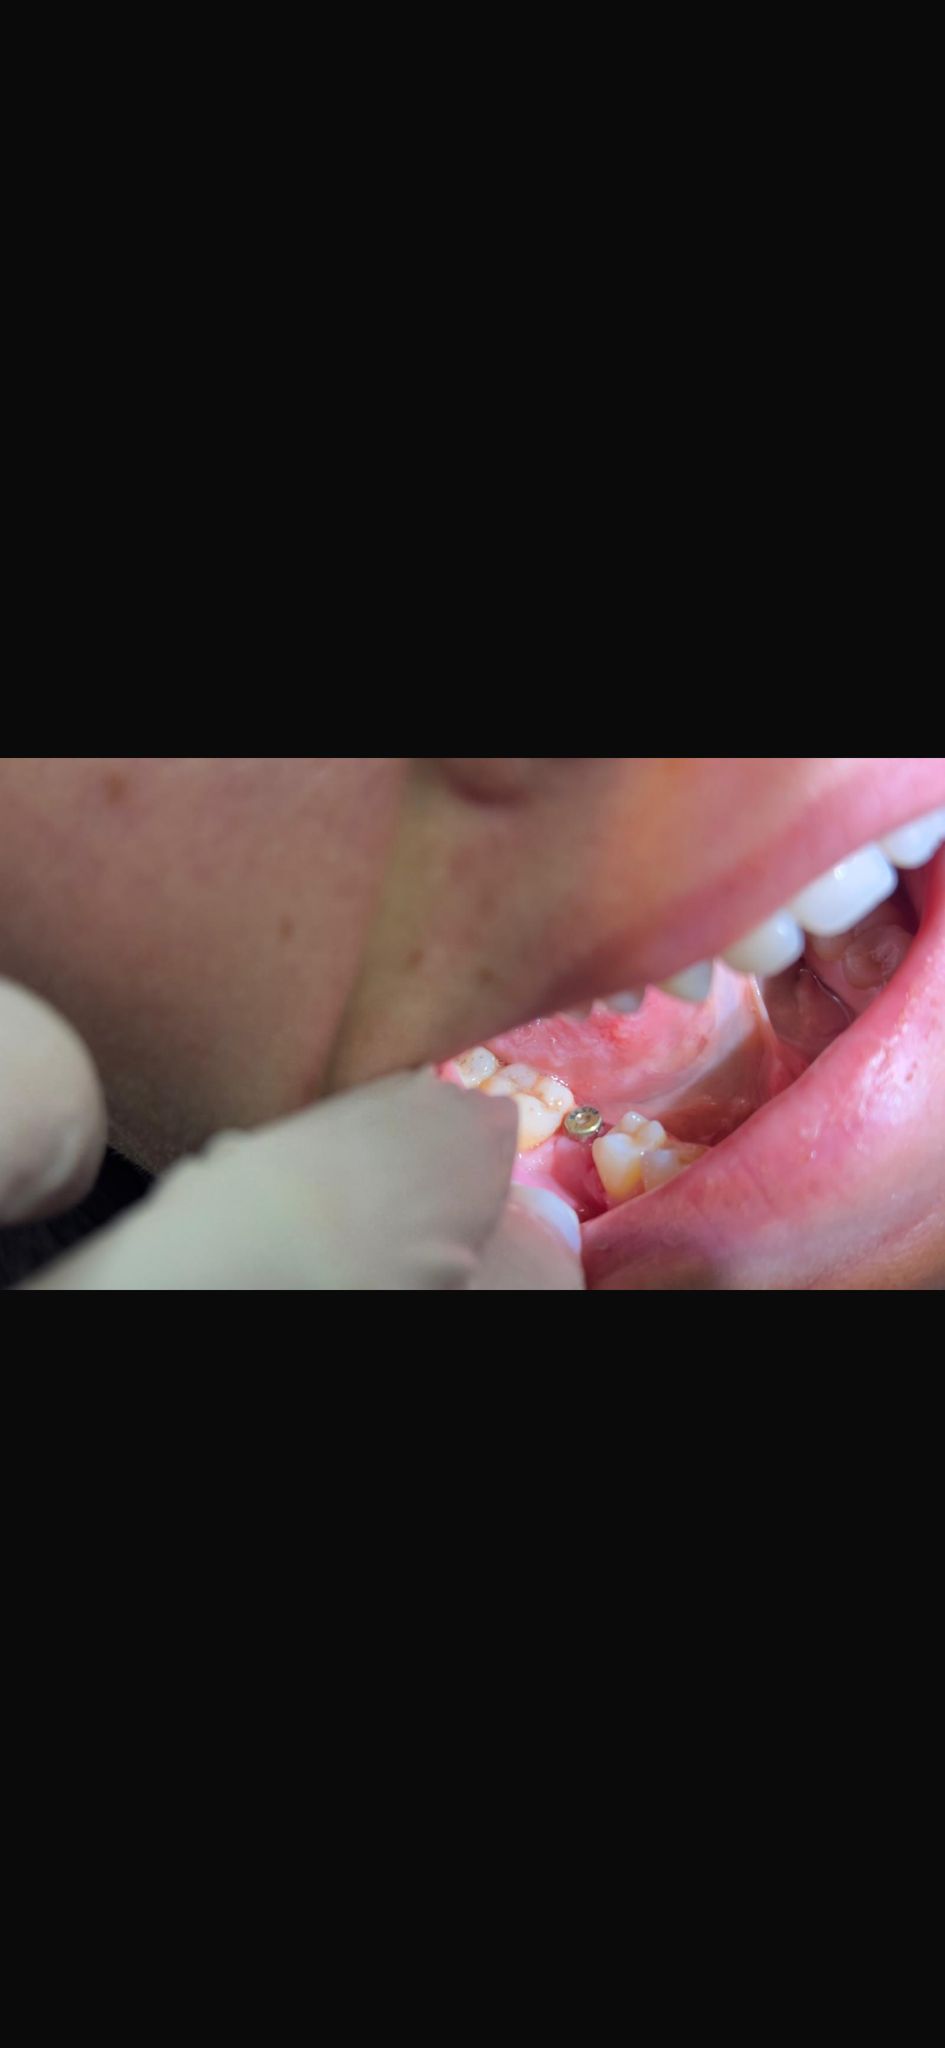

Nesrin Bat ( 01.02.1993) Muayene sonrası alt sağ 1. büyük azı dişinin eksik olduğu tesbit edilmiştir. Gerekli tetkikler sonrasında 3.7 mm çapında bir implant yerleştilmiştir. Osteointegrasyon için beklenmektedir. 29 Eylül Muayene 13 Ocak implant yerleştirildi.